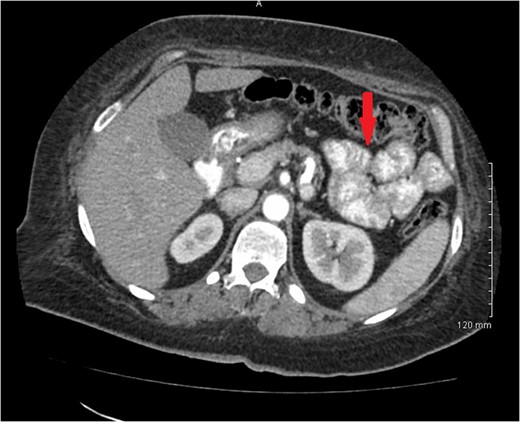

Computerized axial tomography scan of the abdomen revealed wall thickening or mass involving the proximal ascending colon with multiple subcentimeter lymph nodes within mesentery adjacent to this portion (Fig.

1). There was no evidence of metastatic disease. A 3.8 × 3.3 cm hypodense mass located in the central portion of the uterus was also noted (Fig.

Figure 1:

CT scan of abdomen showing ascending colon mass.